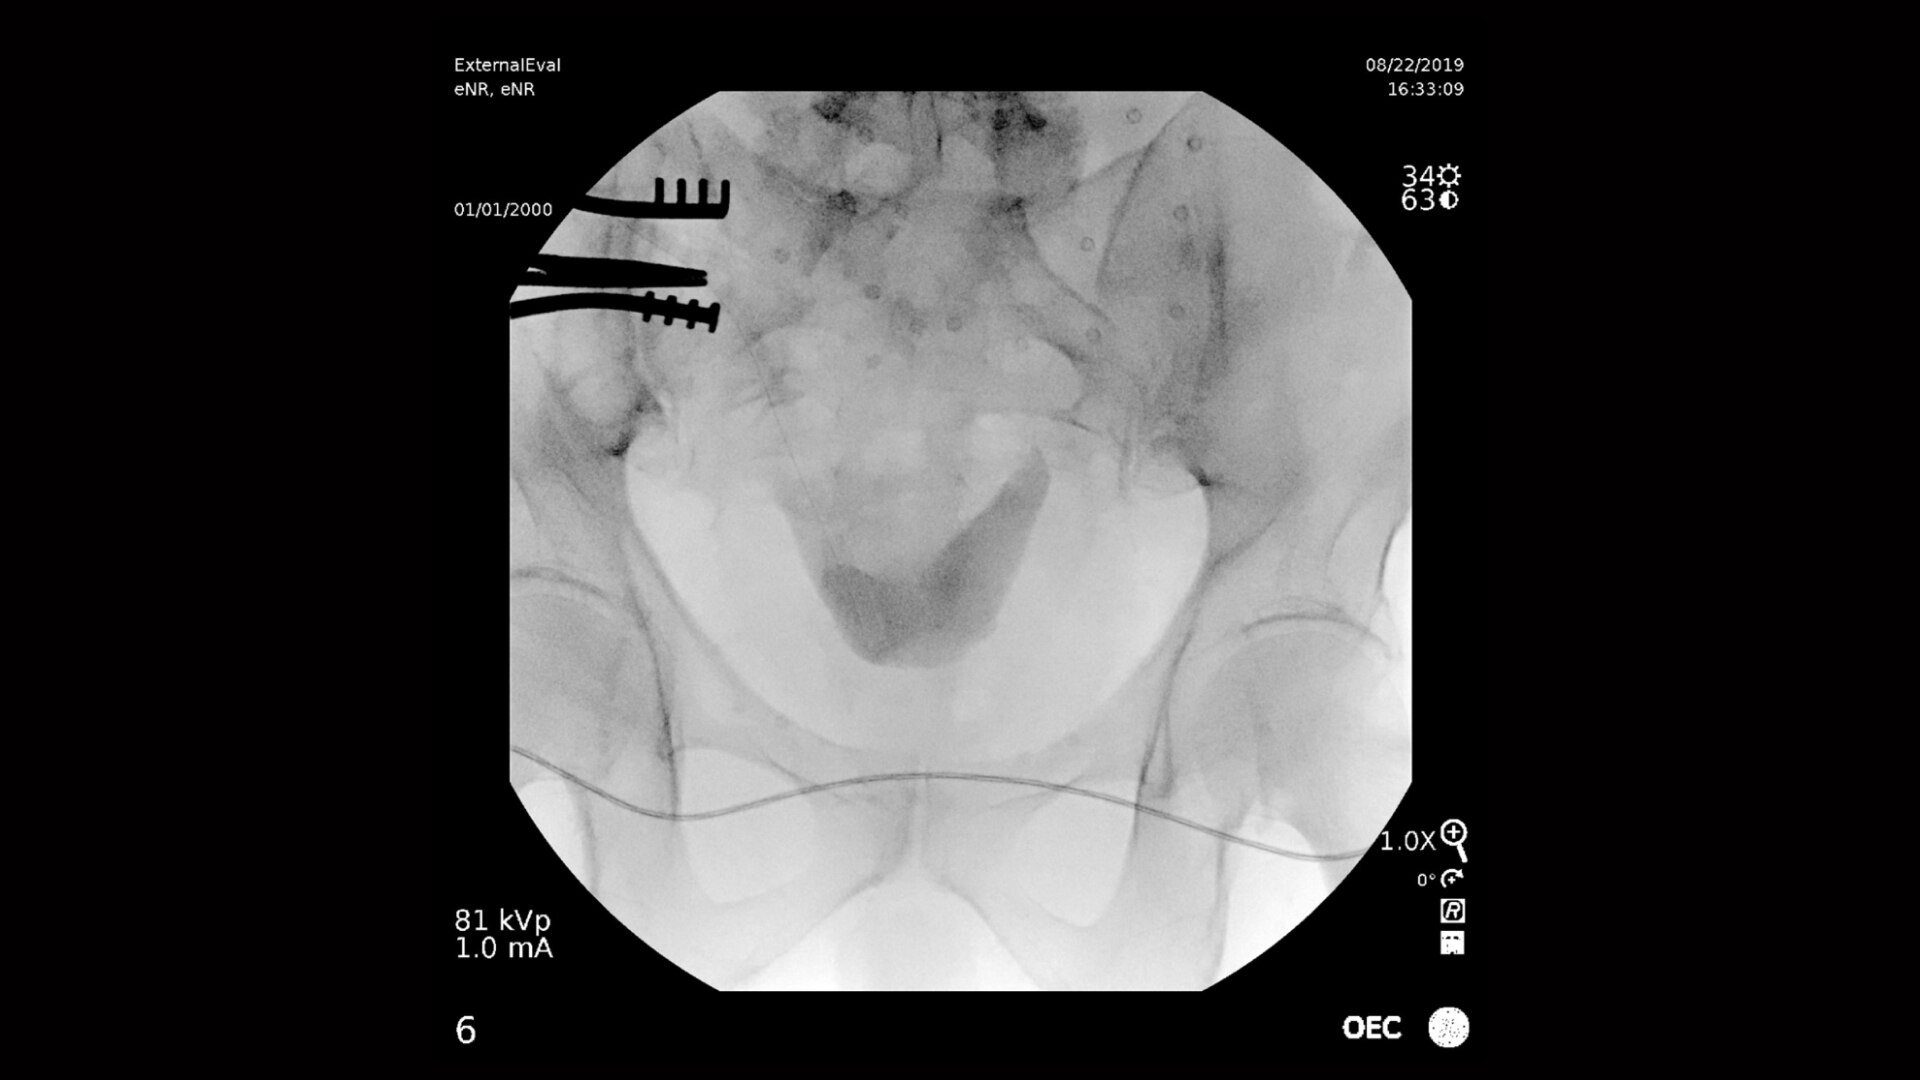

泌尿器イメージングの機能

フラットディテクタから4K UHDディスプレイまでの先進のハードウェア、さらにはOECイメージチェーンにより驚異的な画質を実現します。 General HDプリセットプロファイルを使用することで、エッジ強調された高コントラスト画像が表示されるように最適化され、結石などの微細な構造も適切に確認できます。

Magモードの追加線量やX線管の発熱を伴うことなく透視またはシネ中に最大4倍のライブズームを行うことで、処置中にガイドワイヤやチューブを確認できます。 OEC独自のスプリットブロックデザインを活用することにより、モノブロックCアームを使用した場合よりも検出器を被写体に近づけることができ、最大22%広い視野を確保できます。

複雑な泌尿器系手術には強力なイメージングシステムが必要です。 OECプレミアムCアームは次のような処置で活躍します。 • 腹部血管造影 • 小線源治療 • 膀胱鏡検査 • 静脈性腎盂造影 • 逆行性腎盂造影 • 経皮的腎結石摘出術 • 経尿道的前立腺切除 • 尿力学